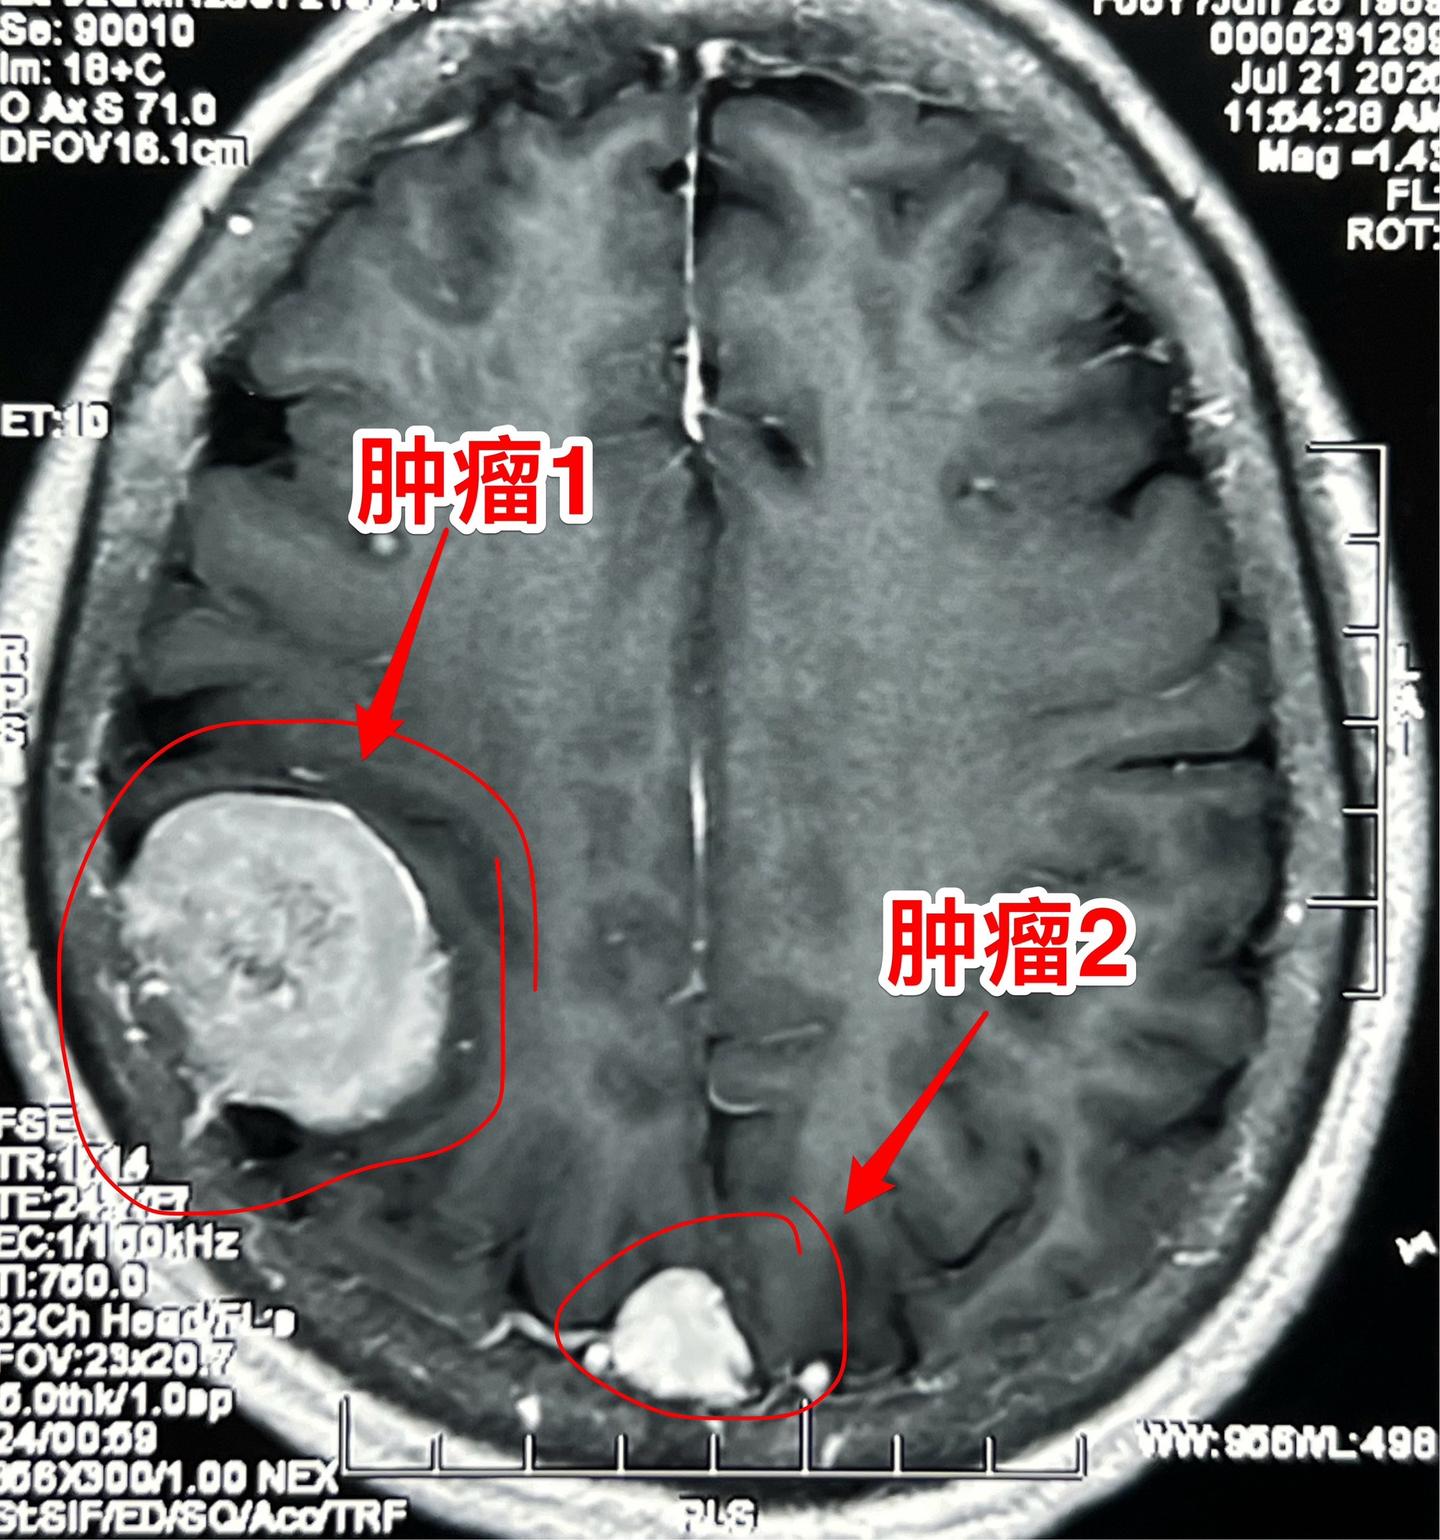

因头痛检查发现脑部有三个瘤。56岁女性,黄梅县人。平时身体很好,因路滑摔倒,检查发现脑部有三个瘤,最大的一个约5厘米。 患者的一个弟弟也是医生,推荐来找我作手术。 如图所示,经过详细的检查,确认第一个、第二个瘤是脑膜瘤,第三个瘤位于垂体窝内,考虑是垂体瘤。 今日(2025年8月3日)作手术,切除了两个脑膜瘤。垂体瘤暂时予以观察。